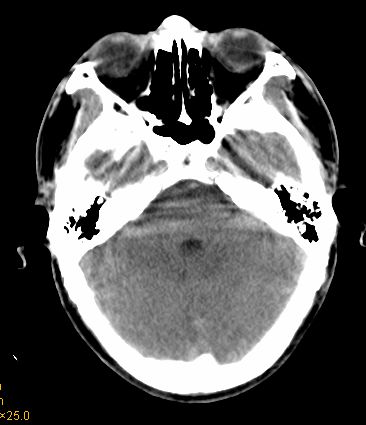

男 42岁 头痛20天

左顶叶见片状低密度影,边界不清,内见斑片状等密度影。考虑转移性肿瘤可能性大,建议ct增强或mr增强扫描。建议胸部检查,排除肺部病变。

左顶叶见片状低密度影,内似见结节状略高密度影,建议增强扫描。

胸部ct未见异常。

左顶叶见片状低密度影,边界不清,内见斑片状等密度影。考虑转移性肿瘤可能性大,建议ct增强或mr增强扫描。建议胸部检查,排除肺部周围型腺癌。